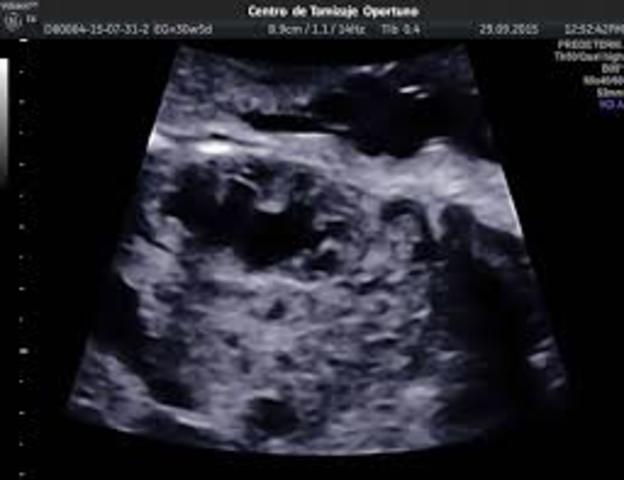

• Ultrasonido

Ultrasonido

Paul Langevin y Chilowsky produjeron el primer generador piezoeléctrico de Ultrasonido cuyo cristal servía como receptor y generaba cambios eléctricos al recibir vibraciones mecánicas.